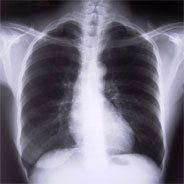

Bei Leiden der Wirbelsäule bemühen sich Ärzte zunächst, sämtliche Optionen der nicht-chirurgischen Therapie auszureizen. Dazu zählen zum Beispiel Medikamente zur Schmerzlinderung, physiotherapeutische Maßnahmen oder der Aufbau der Muskulatur.

Sollte jedoch ein Risiko bestehen, dass durch Verletzungen oder Frakturen der Wirbel Nervenschäden entstehen, die zu Sensibilitätsverlust oder sogar Lähmungen führen könnten, erweist sich ein chirurgischer Eingriff als sinnvoll und eventuell unverzichtbar. In solchen Fällen liegt der Fokus besonders darauf, die Stabilität der Wirbelsäule zu gewährleisten und schwerwiegendere Folgen zu vermeiden.